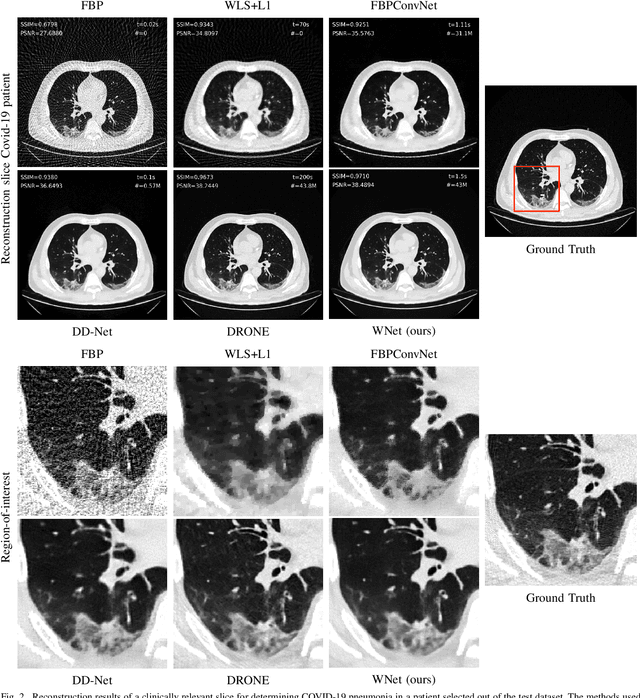

Abstract:Deep learning based solutions are being succesfully implemented for a wide variety of applications. Most notably, clinical use-cases have gained an increased interest and have been the main driver behind some of the cutting-edge data-driven algorithms proposed in the last years. For applications like sparse-view tomographic reconstructions, where the amount of measurement data is small in order to keep acquisition times short and radiation dose low, reduction of the streaking artifacts has prompted the development of data-driven denoising algorithms with the main goal of obtaining diagnostically viable images with only a subset of a full-scan data. We propose WNet, a data-driven dual-domain denoising model which contains a trainable reconstruction layer for sparse-view artifact denoising. Two encoder-decoder networks perform denoising in both sinogram- and reconstruction-domain simultaneously, while a third layer implementing the Filtered Backprojection algorithm is sandwiched between the first two and takes care of the reconstruction operation. We investigate the performance of the network on sparse-view chest CT scans, and we highlight the added benefit of having a trainable reconstruction layer over the more conventional fixed ones. We train and test our network on two clinically relevant datasets and we compare the obtained results with three different types of sparse-view CT denoising and reconstruction algorithms.